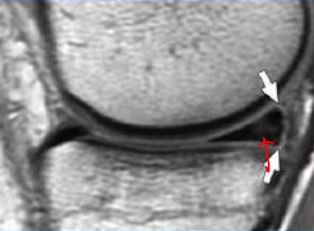

3级(III级):半月板内的高信号达到半月板的关节面,通常代表半月板撕裂。

(III级:半月板线性高信号,达关节面,与关节相同)